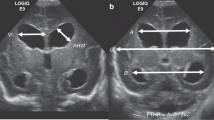

This is a retrospective study of newborns (gestational age <29 weeks) diagnosed with IVH. Clinical variables known to increase the risk for post-hemorrhagic hydrocephalus were collected. The first CUS with IVH was identified and a slice in the coronal plane was selected. The frontal horns of the lateral ventricles were manually segmented. Automated quantitative morphological features were extracted from both lateral ventricles. Predictive models of the need of temporizing intervention were compared.